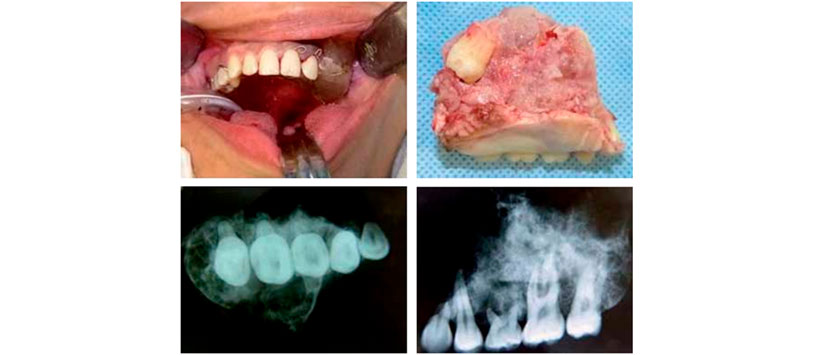

El presente paciente femenino de 20 años de edad, originaria del Estado de México, soltera, católica, estudiante de licenciatura, niega padecer enfermedades crónicas-degenerativas, toxicomanías, alergias o antecedentes importantes para su padecimiento. Acude a valoración refiriendo aumento de volumen en la encía en región de molares superiores izquierdos, con hemorragia ocasional en dicha zona desde hace un año con cinco meses y con crecimiento progresivo. Le realizan biopsia incisional y posterior diagnóstico mediante estudio histopatológico. Refieren compatible con mixoma odontogénico en maxilar izquierdo. Una vez establecido el diagnóstico se procede a realización de protocolo quirúrgico correspondiente

En la tomografía computarizada en cortes axiales en fase contrastada y reconstrucciones multiplanares y en tercera dimensión, se observa lesión en espesor del maxilar del lado izquierdo con infiltración en la totalidad de seno maxilar izquierdo, con diámetro aproximado de 38 mm, heterogénea de bordes mal delimitados con efecto de volumen en la región, observándose órgano dentario en el espesor de la lesión. El perfil perimetral de la lesión extendido hacia fosa pterigoidea y cigomática (Figura 1).

En función con la magnitud y extensión de la lesión, además de su estirpe histológica ya referida, se decide tratamiento de escisión radical de la misma. Siguiendo el protocolo de rutina y bajo anestesia general balanceada por intubación orotraqueal, se procede a realizar infiltración supraperióstica a base de lidocaína a 2% con epinefrina a 1 × 100,000 en región maxilar izquierda y región palatina ipsilateral, con fines hemostáticos y de hidrodisección. Se realiza abordaje circunvestibular y posterior levantamiento de colgajo de espesor total, a continuación se realiza el marcaje del surco donde se realizará la osteotomía, primero en sentido vertical a nivel del canino maxilar izquierdo y posteriormente en sentido horizontal por debajo del agujero infraorbitario izquierdo respetando el piso de la órbita, más tarde se completa corte parasagital en región palatina izquierda, realizando previamente disección de elementos vasculares y nerviosos de la región palatina correspondiente. Finalmente se realiza la maxilectomía parcial izquierda, verificando adecuada hemostasia, observándose bordes libres de lesión a nivel del piso de la órbita izquierda. No hubo pérdida de la continuidad ni evidencia de infiltración hacia la cavidad orbitaria.

Por último se procede a colocar y adaptar el obturador palatino temporal elaborado previamente, fijándolo adecuadamente a órganos dentarios remanentes, observando adecuada estabilidad del mismo, por lo que se concluye el acto quirúrgico (Figuras 2 y 3)